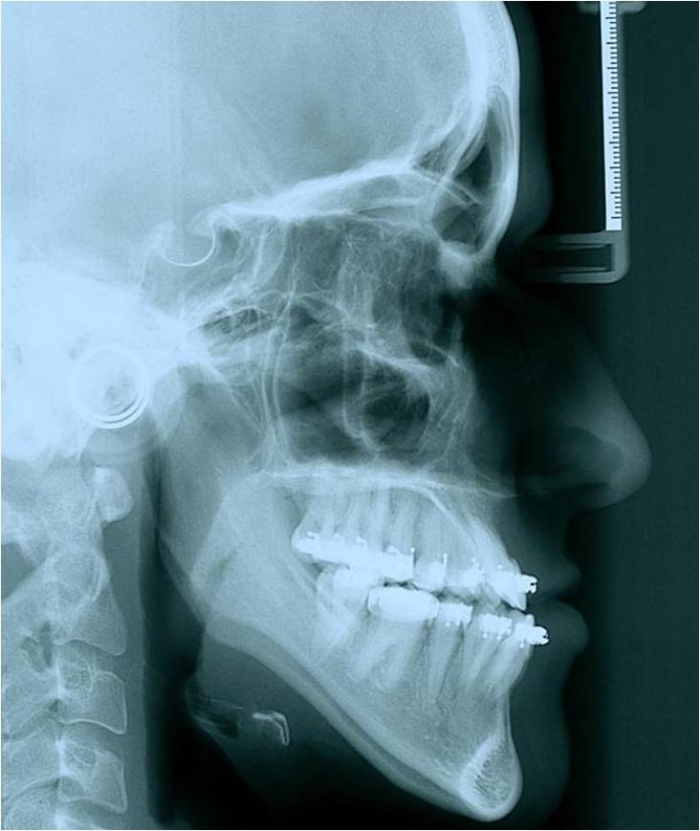

Telerradiografia inicial - Clínica Cliniface

Telerradiografia inicial

Telerradiografia após a cirurgia - Clínica Cliniface

Telerradiografia após a cirurgia